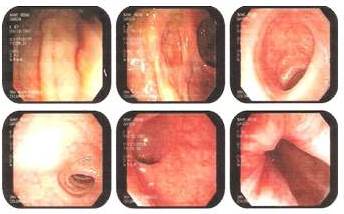

Uretrocistocopia 03/07/2008: lesión tumoral en introito vaginal, la uretra anterior se observa modificada, levantada por lesión amamelonada ocupando introito vaginal, meato uretral desplazada, resto del estudio normal.